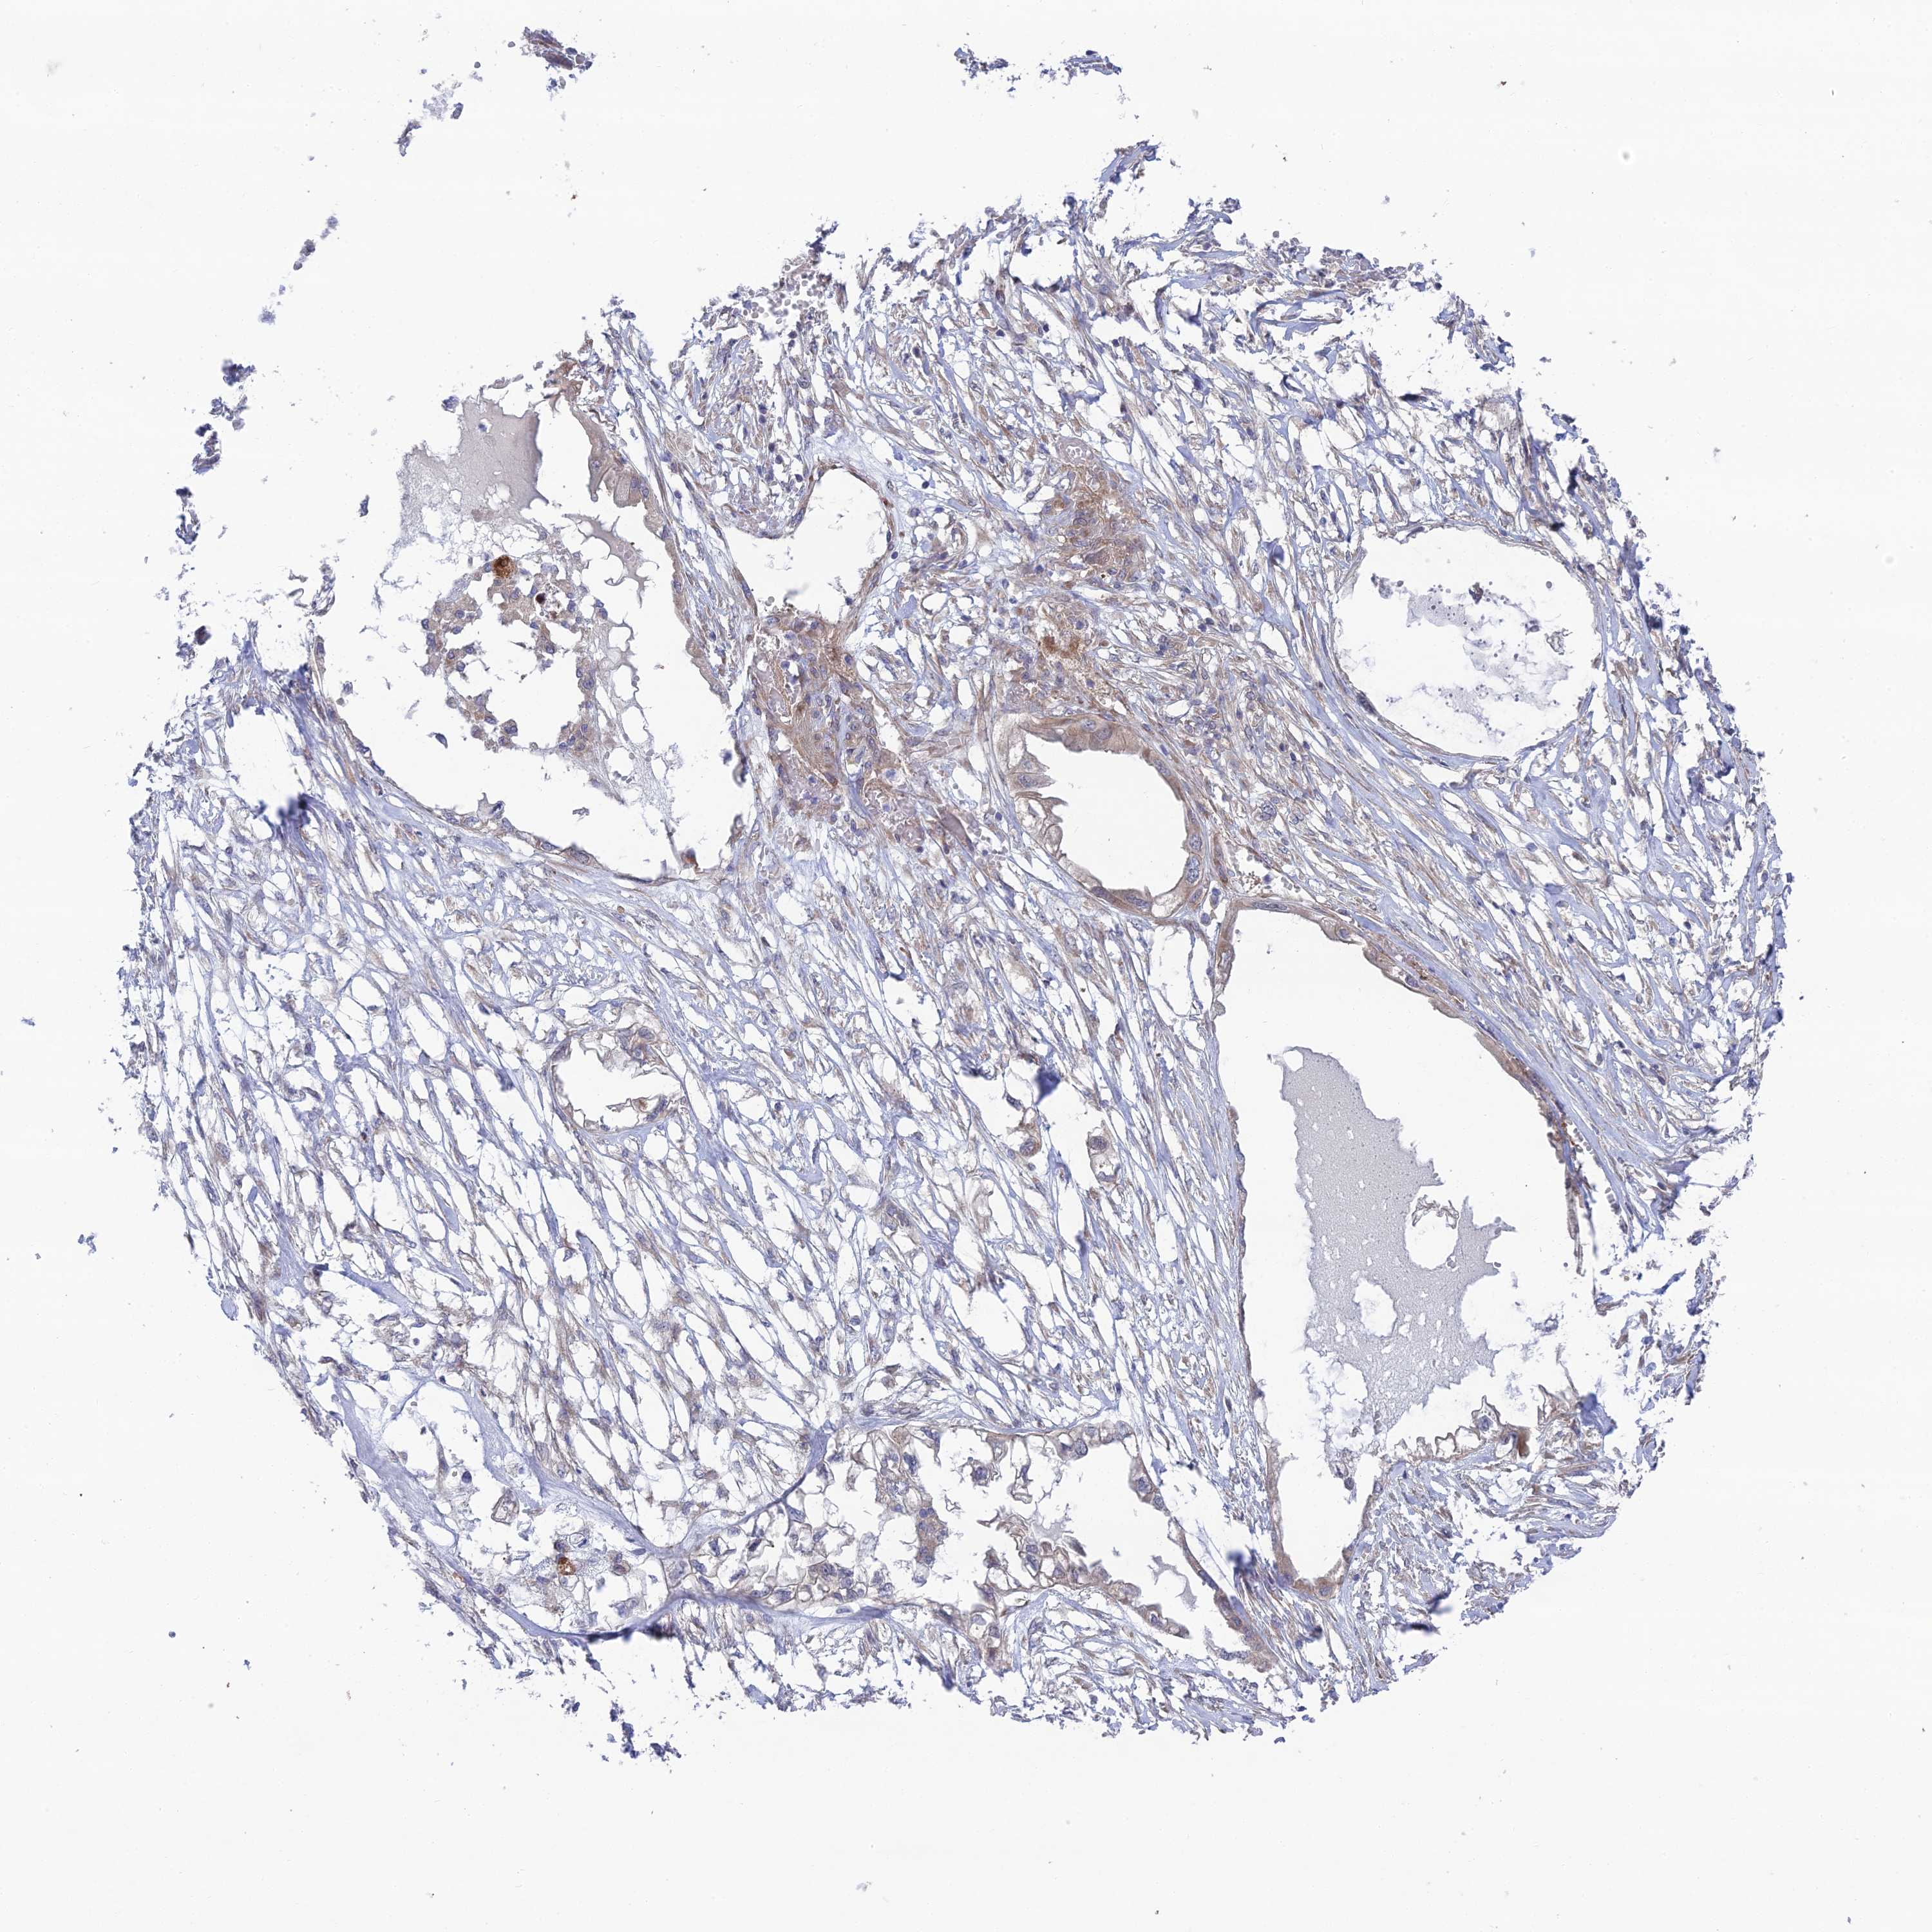

ENDOMETRIAL CANCER - Protein expressioni

A mouse-over function shows sample information and annotation data. Click on an image to view it in a full screen mode. Samples can be filtered based on level of antibody staining by selecting one or several of the following categories: high, medium, low and not detected. The assay and annotation is described here.

Note that samples used for immunohistochemistry by the Human Protein Atlas do not correspond to samples in the TCGA dataset.

Antibody stainingi

Antibody staining in the annotated cell types in the current human tissue is reported as not detected, low, medium, or high, based on conventional immunohistochemistry profiling in selected tissues. This score is based on the combination of the staining intensity and fraction of stained cells.

Each image is clickable and will lead to virtual microscopy that enables deeper exploration of all samples and also displays staining intensity scores, fraction scores and subcellular localization as well as patient and tissue information for each sample.

Antibody HPA044359

Staining

High

Medium

Low

Not detected

Intensity

Strong

Moderate

Weak

Negative

Quantity

>75%

75%-25%

<25%

None

Location

Nuclear

Cytoplasmic/membranous

Cytoplasmic/membranous,nuclear

Adenocarcinoma, NOS

Adenocarcinoma, metastatic, NOS